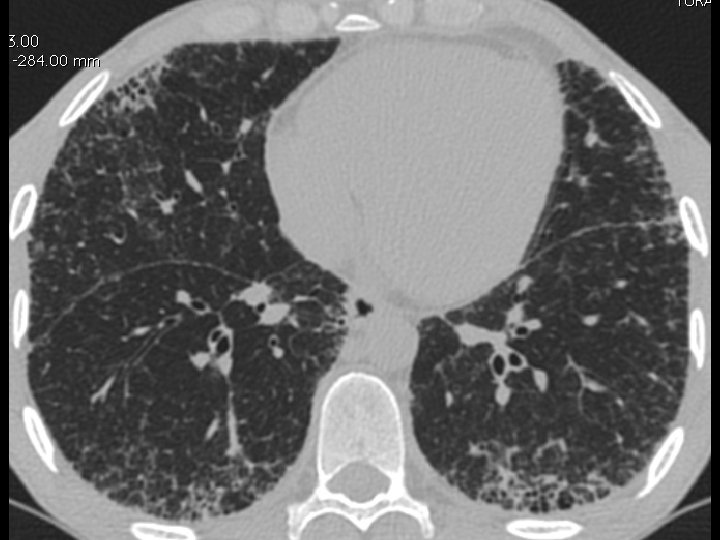

High-resolution CT scan

Subpleural, basal predominance Reticular abnormality Honeycombing with traction bronchiectasis UIPUIP Pattern

Subpleural, basal predominance Reticular abnormality Honeycombing with traction bronchiectasis Profuse micronodules UIPUIP Pattern Inconsistent with UIP Pattern

39 yo caucasian male, works in car collision repair and painting Multiple allergies, Gastroesophageal reflux disease and Thrombocytopenia of unknown etiology Smoker. No drugs CT: Reticular abnormality and honeycombing of subpleural basal predominance + micronodules Lung function tests: decreased diffusion capacity of the lung Blood tests: small increase of ESR and CRP; Autoimmune screening blood tests were normal BAL: normal celularity, with a mild increase in the neutrophil and eosinophil count

39 yo caucasian male, works in car collision repair and painting Multiple allergies, Gastroesophageal reflux disease and Thrombocytopenia of unknown etiology Smoker. No drugs CT: Reticular abnormality and honeycombing of subpleural basal predominance + micronodules Lung function tests: decreased diffusion capacity of the lung Blood tests: small increase of ESR and CRP; Autoimmune Screening Blood Tests were normal BAL: normal celularity, with a mild increase in the neutrophil and eosinophil count Definitive diagnosis can be established? Additional diagnostic tests required? Which tests?